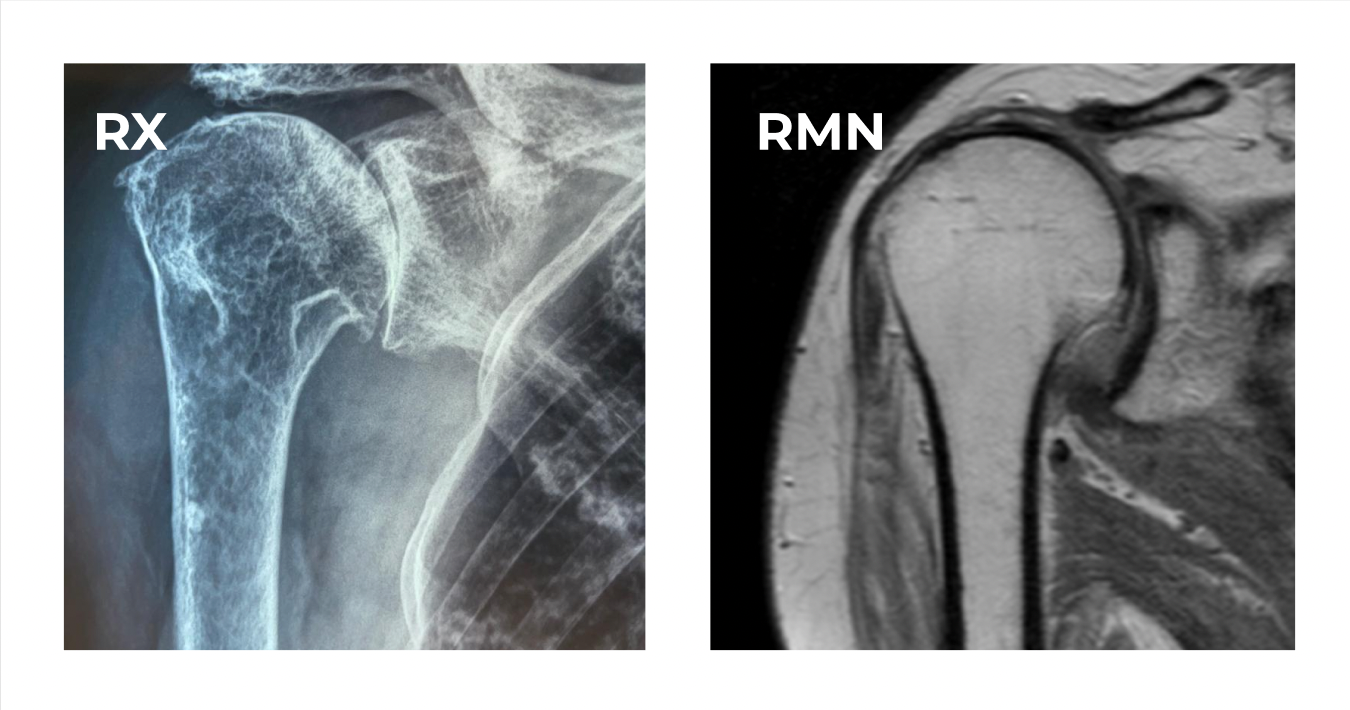

Diagnosi di artrosi spalla

L’esame obiettivo, insieme agli esami strumentali, conduce lo specialista ad una diagnosi di certezza:

Per valutare l’entità e il grado di artrosi lo specialista si avvale di esami strumentali per valutare: esame radiografico delle spalle, TC e/o RMN.